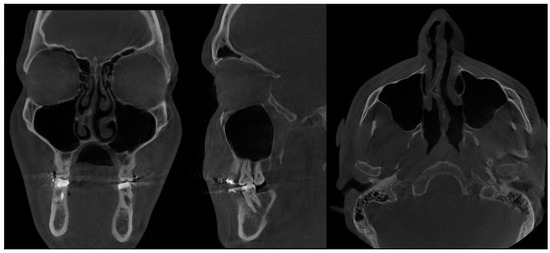

- Type 2 in-pure SSS (iSSS) (Figure 3, Figure 4 and Figure 6) related to maxillary deformation (might be related to maxilla-mandibular skeletal class II/III deformities or others), clinically asymptomatic, not related to trauma or surgery, 1–3 MS walls retracted, OMC clear, no opacification, like suggested by Lee et al., the “not so silent sinus” [18];